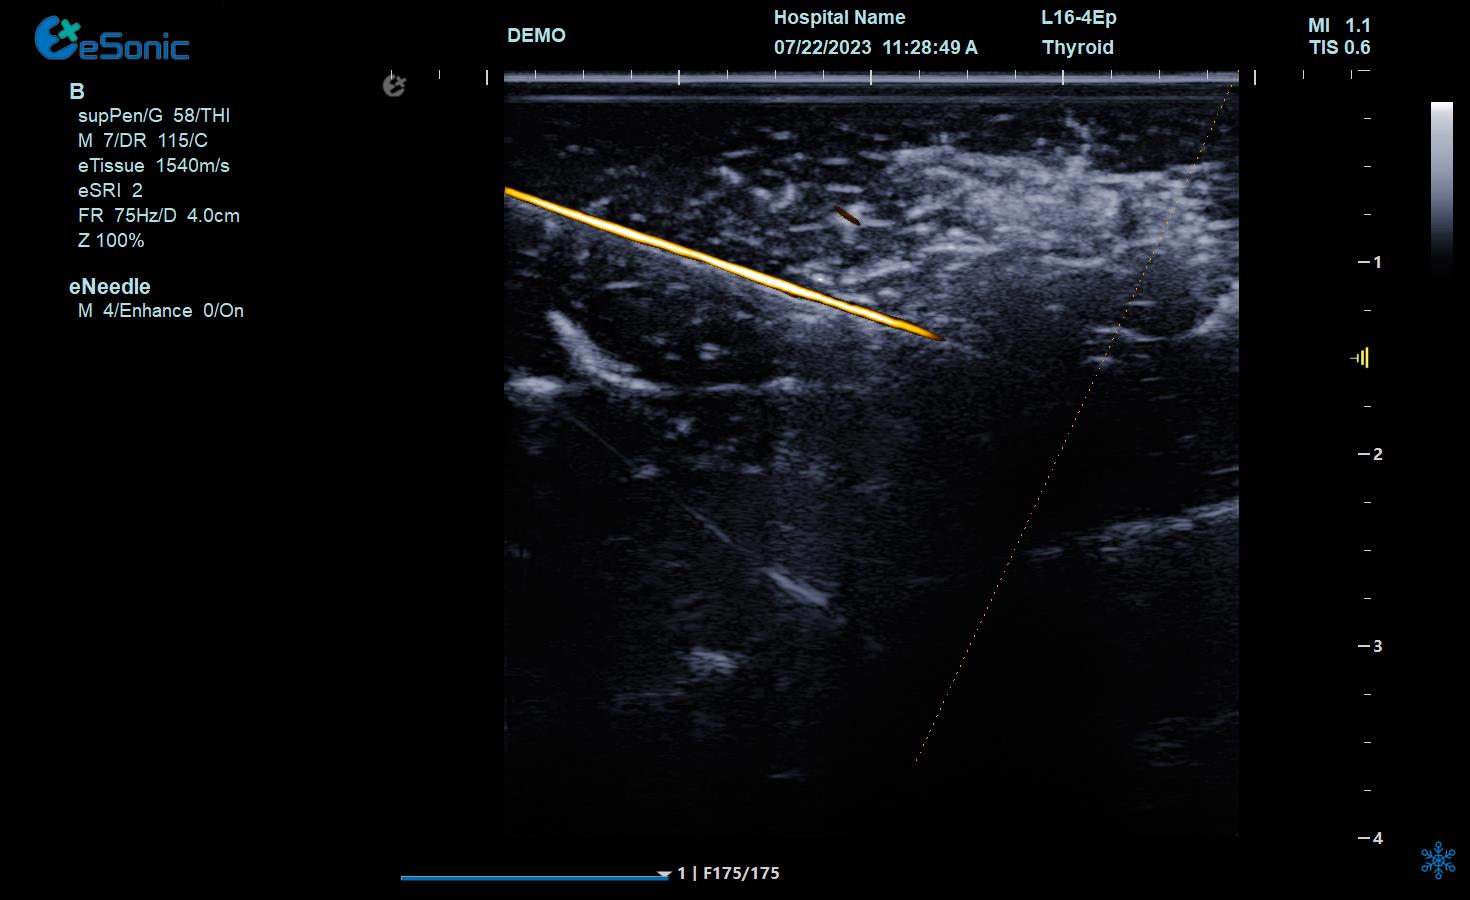

神经阻滞

穿刺智能map